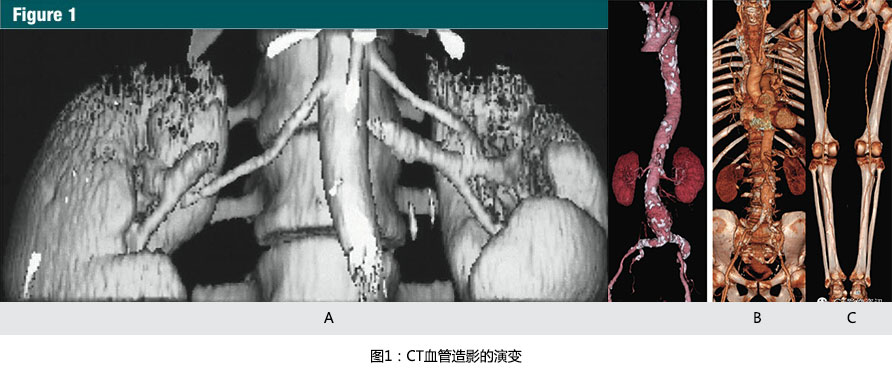

在1991年到1998年,由于單排螺旋CT的掃描速度限制了CTA進入到各個不同的血管領域。采用大(dà)于1的掃描螺距之前,一(yī)個層厚3mm,30秒的掃描,最大(dà)覆蓋的範圍是9cm,因此,限制了在頸外(wài)動脈(10)、Willis環(11),腎動脈(12,13)(圖 1a)及近端腹主動脈(13)中(zhōng)的早期應用。

From 1991 to 1998, single-detector row spiral CT technique limitedclinical CT angiography to discrete vascular territories. Prior to the introduction of scan pitch values greater than one, a scan with 3-mm nominalsection thickness provided a maximum of 9 cm table travel in 30 seconds andthus limited initial applications to the extracranial carotid arteries (10),the circle of Willis (11), the renal arteries (12,13)(Fig 1a), and the proximal abdominal aorta(13).

1998年推出的早期多排探測器CT具有4排探測器和0.5s的旋轉時間,對于相同層厚,單位時間增加了8倍的容積覆蓋範圍(8,23)(圖 1b,1c)。

Early multi-detector row CT scanners introduced in 1998 had four detector rings and were capable of 1/2-second gantry rotations, effectively multiplying volume coverage per unit time 38 at the same section thickness (8,23)(Fig 1b, 1c).

摩爾定律也直接成為CT血管造影(CTA)最終臨床應用的推動者:因為一(yī)層接着一(yī)層的CTA圖像并不有效和直觀,可視化的CT血管造影包括表面遮蓋顯示,最大(dà)密度投影,和容積再現(VR)(圖1b,1c)。

Moore's law is also directly responsible for the final enabler of clinicalCT angiography: Because section-by-section inspection of CT angiographic imagesis neither efficient nor intuitive, visualization of CT angiography studies employs shaded surface displays, maximum intensity projections, and volume rendering (Fig 1b, 1c).

(A):1991年12月獲得的腎動脈CT血管造影圖像。9厘米的縱向覆蓋,采用3mm的準直線束需要30秒螺旋掃描時間。當時,表面遮蓋技術是唯一(yī)的三維顯示手段。最大(dà)密度投影和容積再現成像需要在高度專業的計算機系統上進行脫機處理(參考文獻13)

(B):随着1998年的四排螺旋CT的引進,使主動脈-髂動脈系統(從胸廓入口開(kāi)始直到腹股溝)作為一(yī)個整體(tǐ)僅通過一(yī)次圖像采集并成像成為了可能。容積再現技術所展示的CTA圖像,使用4x2.5mm的螺旋掃描模式在28秒内掃描完成。圖片充分(fēn)顯示了主-髂動脈鈣化和腹主動脈瘤(參考文獻8)

(C):2001年使用容積再現技術展示的CTA圖像,使用16 x1.25毫米螺旋掃描模式,僅用了21秒的時間,就完成了從顱底至踝的動脈系統掃描,離(lí)1991年第一(yī)例螺旋CT的CTA成像隻隔了10年,但是CT的掃描速度則增加了近25倍。